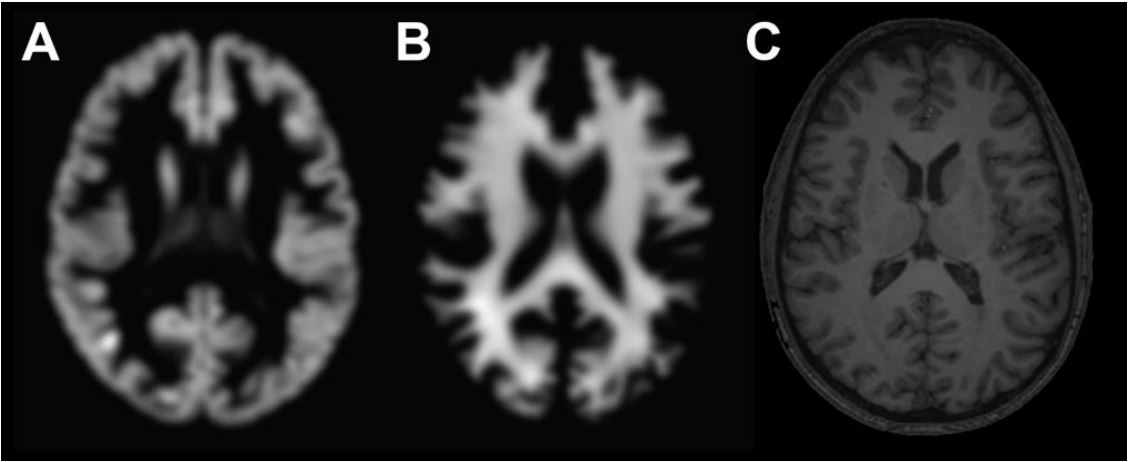

Cada imagen es un escaneo estándar de resonancia magnética ponderada al T1, similar a las que producen la mayoría de las máquinas de resonancia magnética modernas. Cada escaneo está etiquetado con la edad cronológica del paciente.

El equipo utilizó el 80% de estas imágenes para entrenar una red neuronal convolucional para determinar la edad de una persona a partir de su escaneo cerebral. Y el otro 20% de imágenes se empleó para validar este proceso. Por último, la testearon con otras 200 imágenes que la máquina no había visto anteriormente para determinar su precisión.